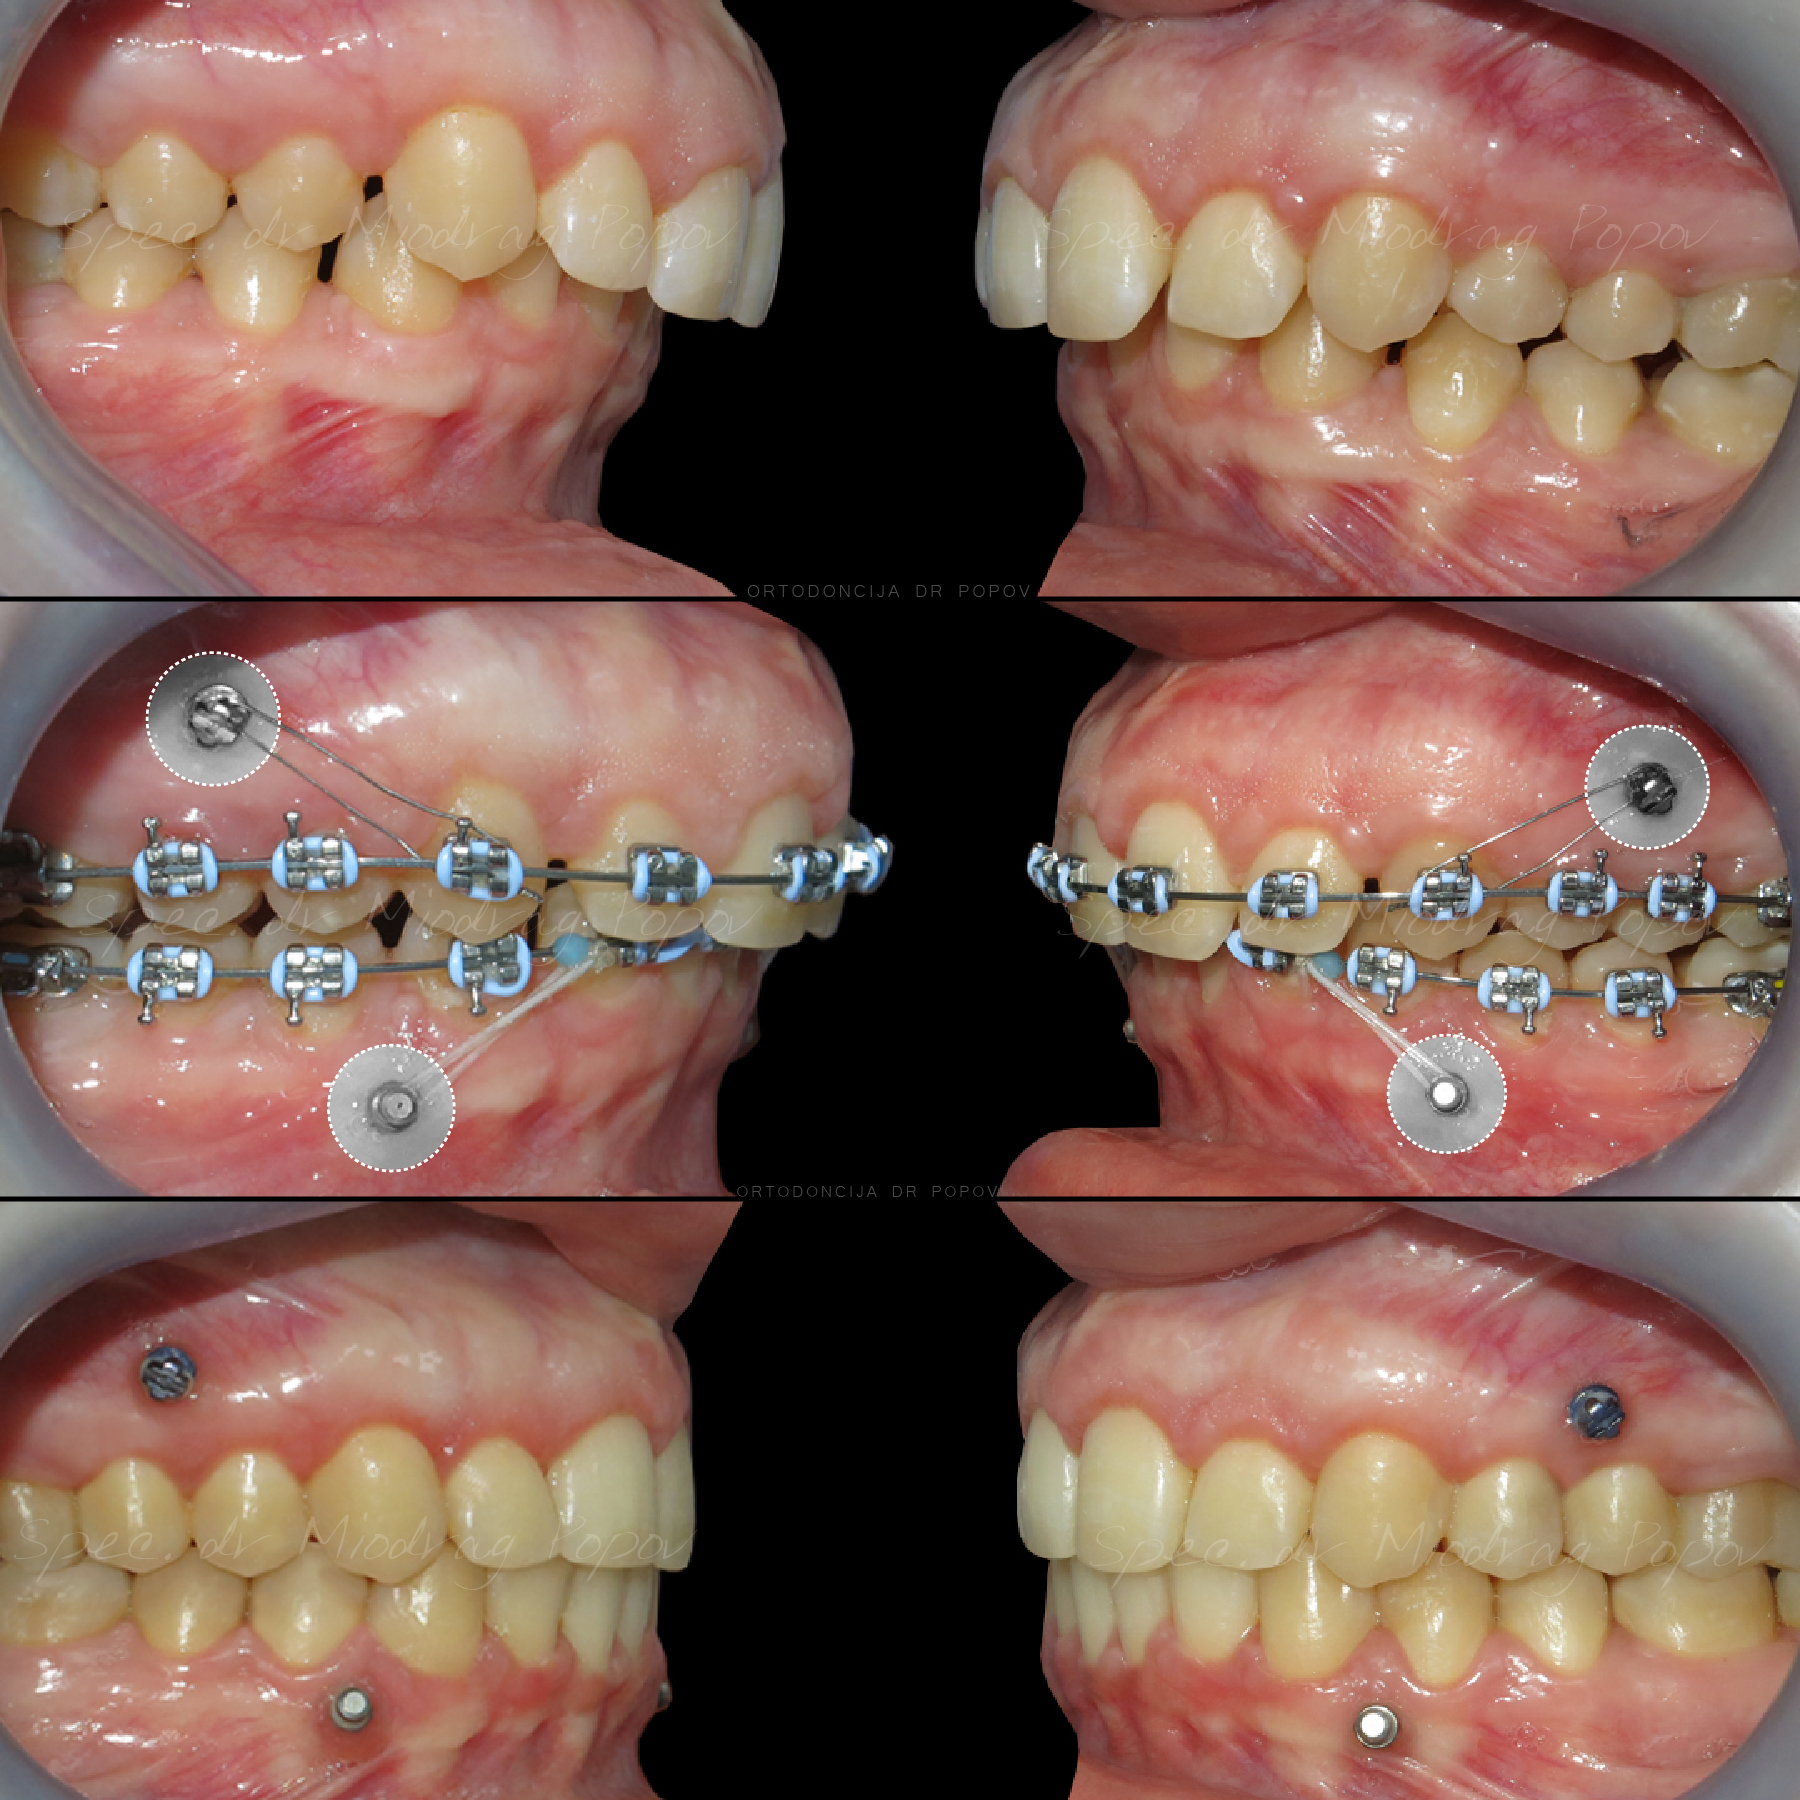

Na početku ortodontske terapije uvek se prvo uspostavilista problema i ciljevi ortodontske terapije na osnovu kojih se pravi mehanički plan.

Takav plan se postepeno korak po korak sprovodi u delo.

U ovom slučaju glavni problemi su bili:

- Distalan zagrižaj

- Nagnuta okluzalna ravan

- Asimetričan gummy smile

- Neslaganje sredina zubnih nizova

Svi zajedno smo se trudili i na kraju smo uspeli da dobijemo prelep rezultat.